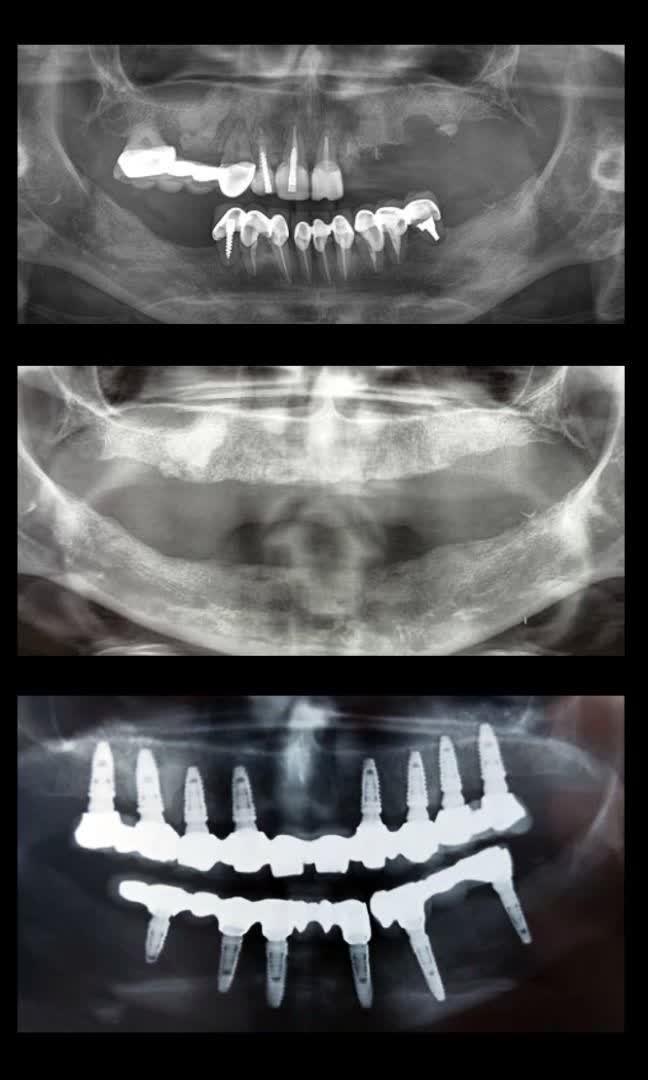

نمونه کارهای قبل و بعد از کاشت ایمپلنت دندان